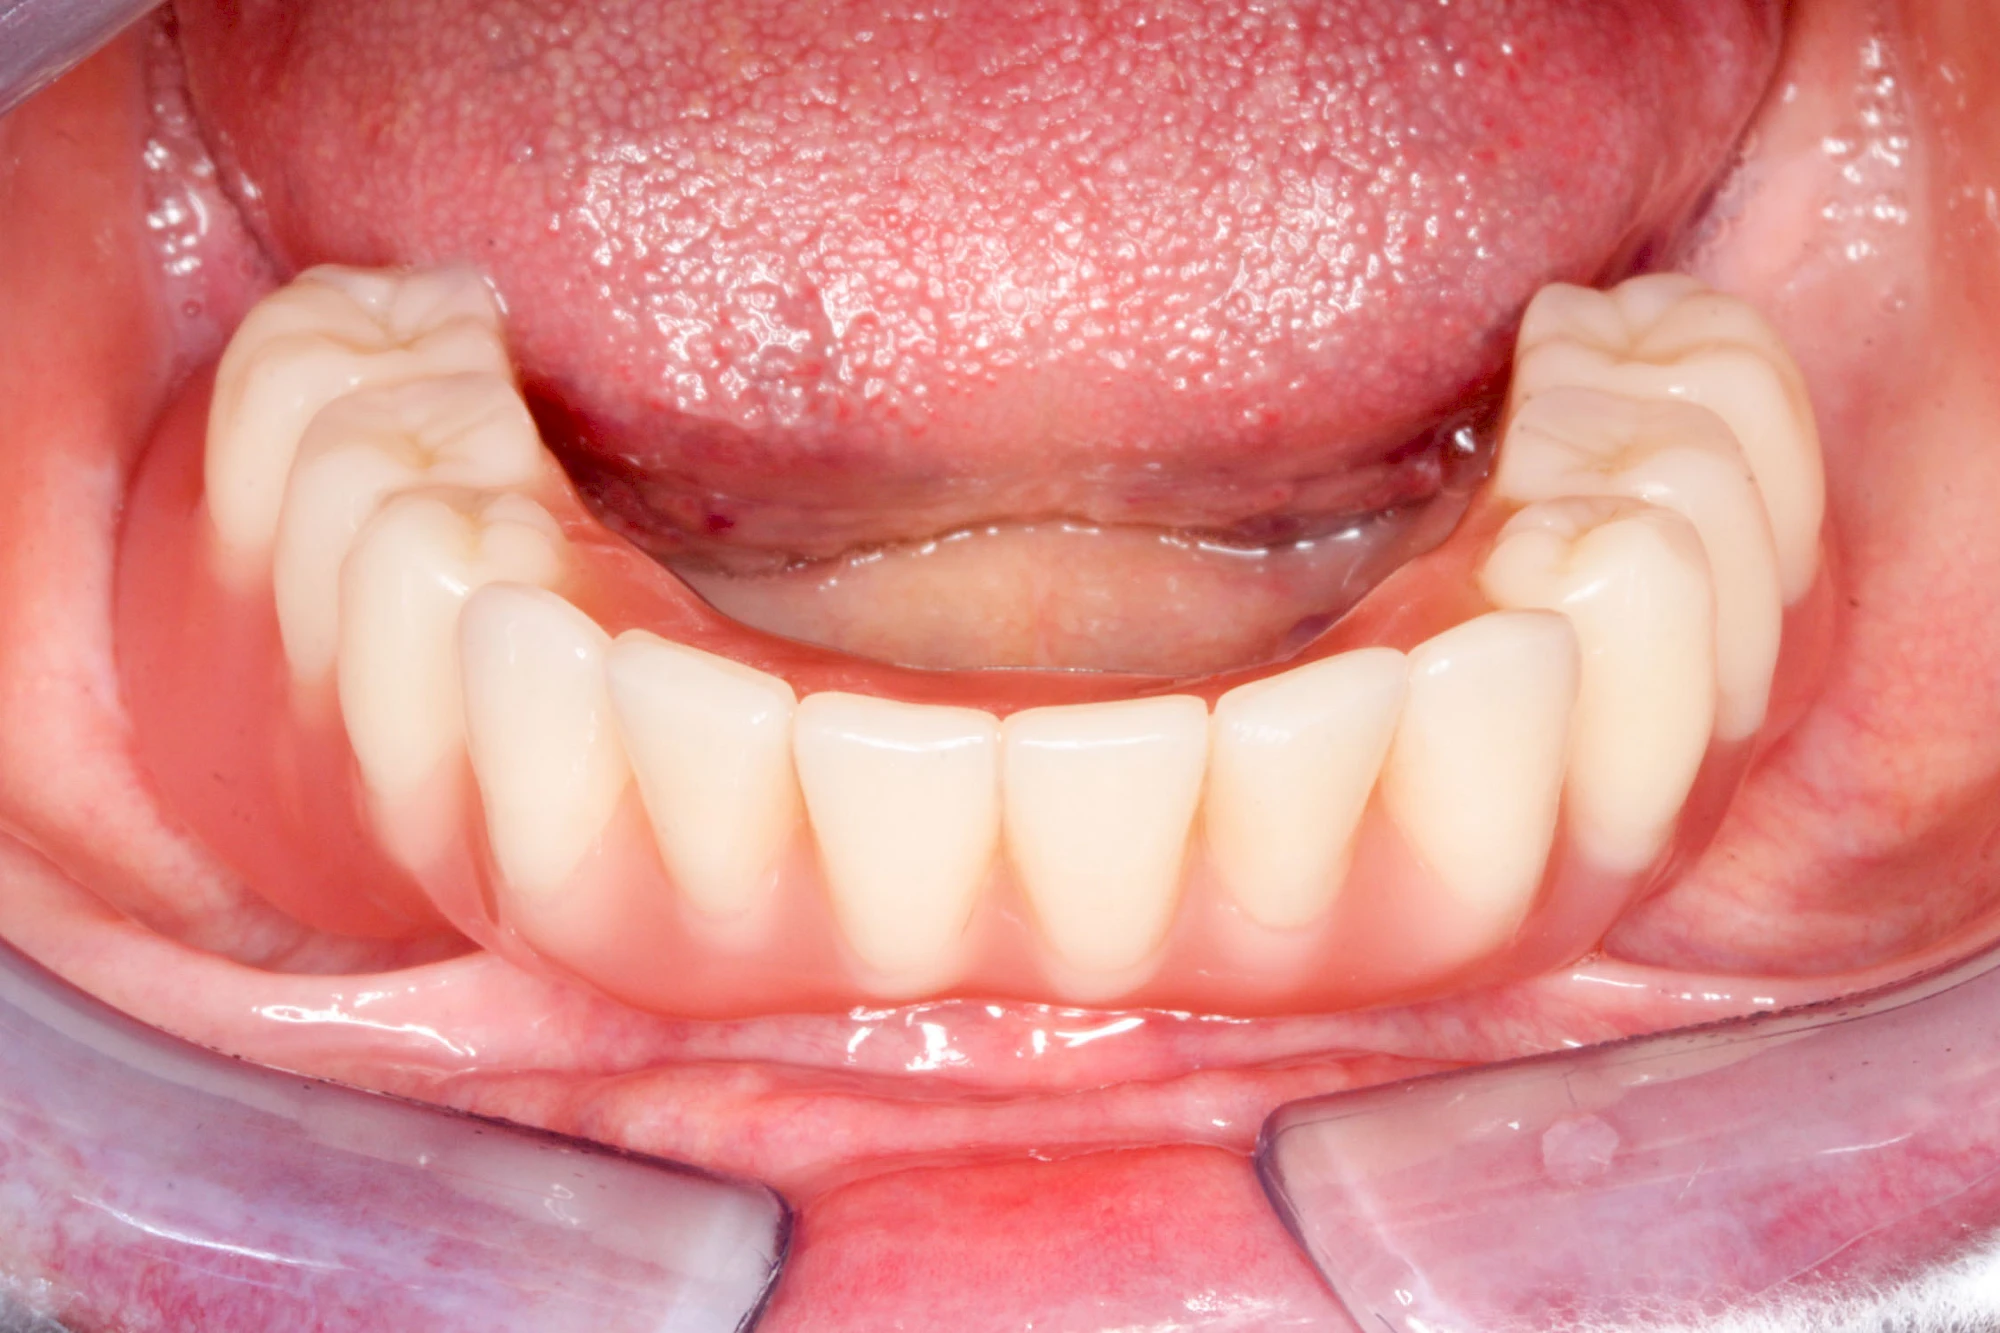

Bei herausnehmbaren Prothesen werden Implantate eingesetzt, um den Halt und den Tragekomfort der Prothesen zu verbessern. Dazu kommen verschiedene Verbindungselemente zum Einsatz:

- Teleskope

- Kugelköpfe

- Tellerförmige Lokatoren

- Stege

- Magnete (selten)

Neben rein implantat-getragenen zahnärztlichen Versorgungen werden bei herausnehmbaren Prothesen Implantate auch in Sinne einer "strategischen Pfeilervermehrung" ergänzend zu eigenen Zähnen zur Verankerung eines Zahnersatzes genutzt.

Varianten zur Verankerung von abnehmbarem Zahnersatz auf Implantaten